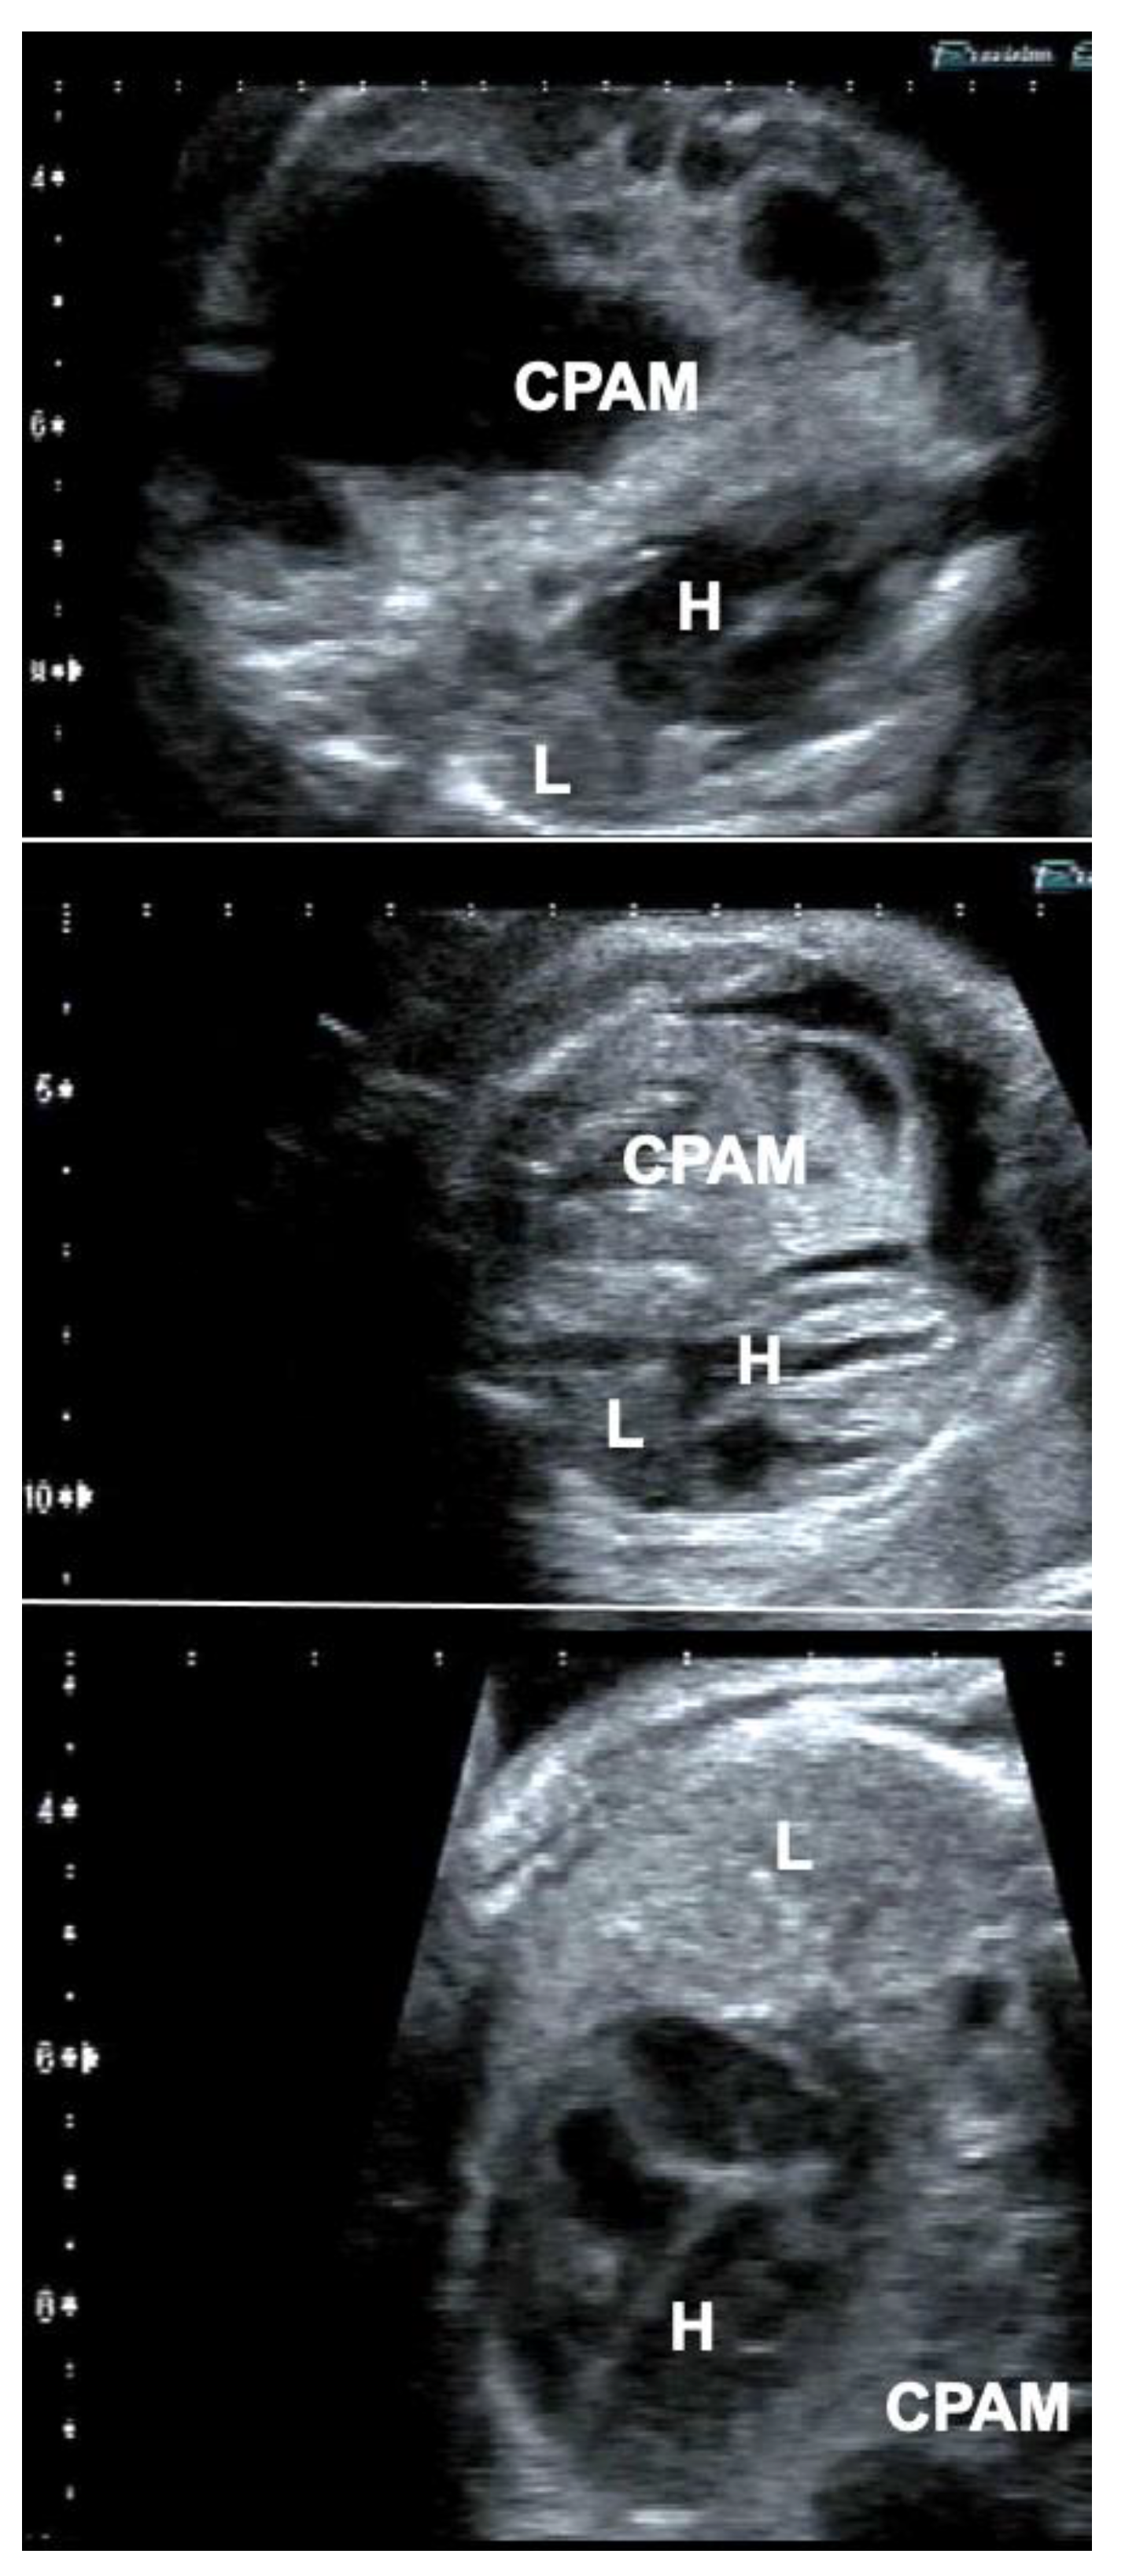

Figure 6.

Effect of FETO in a fetus with a giant congenital pulmonary airway malformation (CPAM) (top), whose lungs did not distend—despite several previous interventions—after long-standing compression and were considered too small or too dysfunctional for postnatal survival (middle). In this case, FETO at 30 + 4 weeks of gestation served as the last resort to achieve lifesaving lung catch-up growth (bottom). H = heart; L = lung.